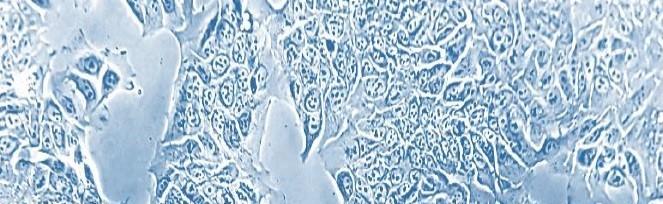

Cancer cells. Photo: Caroline Hild Pettersen